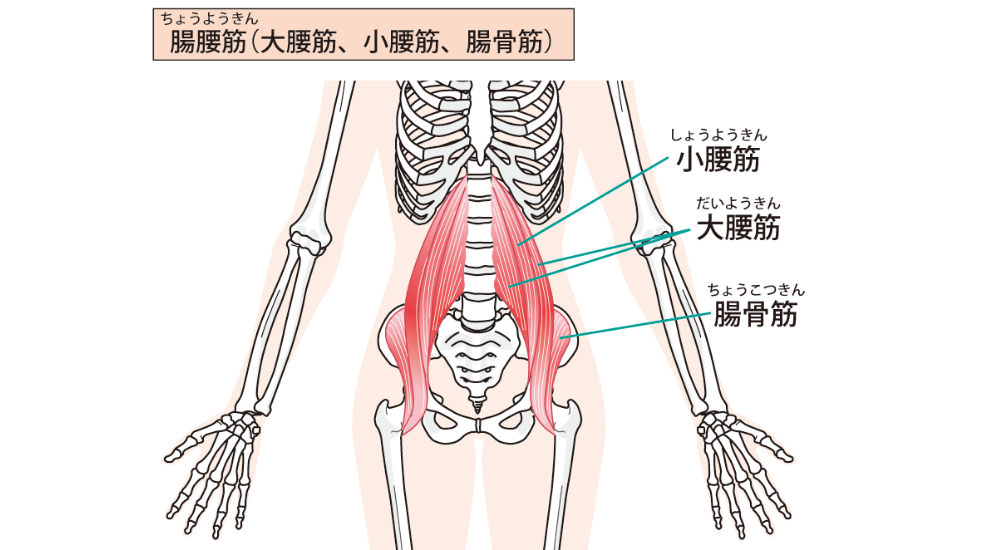

原因: 骨盤の過度な前傾が主な原因です。長時間座る姿勢による股関節前面の筋肉(大腰筋など)の短縮・硬化、腹筋や大臀筋といった体幹やお尻の筋肉の弱化、ハイヒールの常用、妊娠による体型の変化などが挙げられます。

- 大腰筋・腸骨筋(腸腰筋): 腰椎から股関節前面にかけての筋肉。長時間座る姿勢で短縮・硬化しやすく、骨盤を前傾させ、反り腰を助長し、腰痛の原因となります。